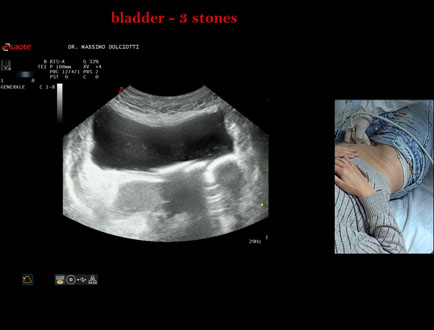

Data inserimento: 21/10/2025

Ecografia del: 15/10/2025

Strumento: Esaote MyLab Eight

Sonda: Convex Multifrequenza 1-8 MHz

Età Paziente: F 45 anni

Motivazione dell'esame: da alcuni mesi, disuria ed infezioni urinarie recidivanti.

Commento all'esame: le immagini ed il video documentano 3 immagini iperecogene, con cono d'ombra posteriore, da ricondurre a litiasi multipla della vescica.

Conclusioni: 3 calcoli della vescica (3 bladder stones).